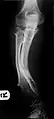

| Photograph of the legs of a 26-year-old male showing multiple lumps leading to deformity. | |

Multiple osteochondromas causing deformity of the forearm (shortening of the Radius with secondary bowing of the Ulna).